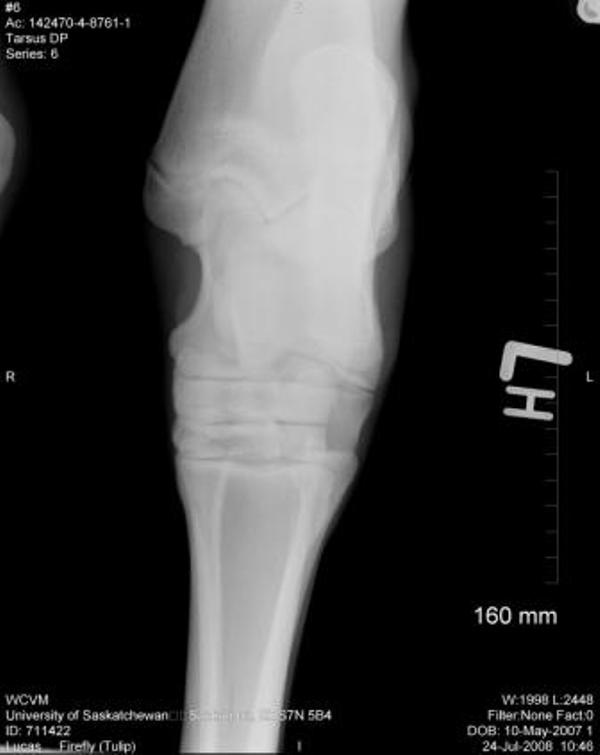

Bilateral Tarsi:

Left Tarsus:

There is a small osseous protrusion off of the distal aspect of the medial trochlear ridge. This is a normal variation. There is also a very small linear osseous fragment visible dorsal to the proximal intertarsal joint in the lateral view This may be a normal finding or it may be a small osseous fragment from more proximity in the tarsus. No Obvious defect or origin of this fragment is noted, however.

As there were some left hock abnormalities noted, I am now posting her hock pictures.